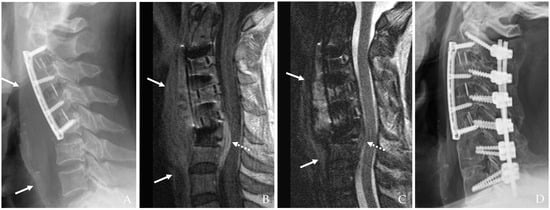

MRI with contrast enhancement is highly effective in differentiating postoperative changes from active infectious processes, particularly when complications such as epidural abscess, osteomyelitis, or spinal cord compression are suspected [17,21,24]. MRI’s high soft tissue contrast resolution is indispensable for evaluating deep-seated infections (Figure 3). Diffusion-weighted imaging (DWI) and dynamic contrast-enhanced MRI are increasingly employed to improve sensitivity in detecting infection-related changes [15]. Furthermore, advanced imaging techniques, such as 3D reconstruction and volumetric assessment, can enhance the detection of subtle pathological changes and guide surgical planning [16] (Figure 3).

Figure 3. The patient underwent C5-6-7 anterior cervical discectomy and fusion (A). At postoperative 2 months, postoperative infection occurred, and magnetic resonance images showed retropharyngeal (white arrows) and epidural (dotted white arrows) (BD).